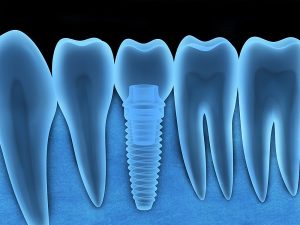

Un implante dental es una raíz artificial de titanio que colocamos en los huesos alveolares de los maxilares, superior o inferior (mandíbula) y que se adapta completamente con los tejidos de la boca. El objetivo y finalidad de los implantes es servir de soporte a una corona o prótesis que sustituirá a piezas dentales que hayamos perdido o que estén muy deterioradas.

Trabajamos con implantes dentales de titanio de la mayor calidad, 100% biocompatibles, por lo que prácticamente es inexistente la posibilidad de rechazo.